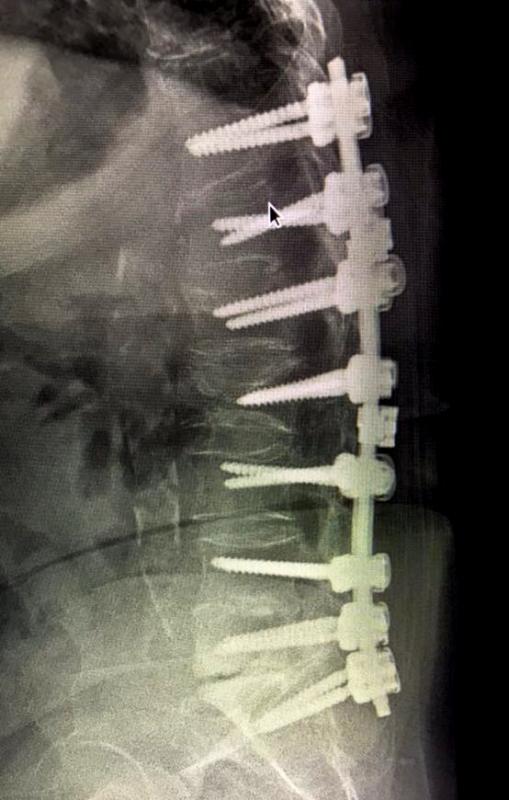

REBORN SPINAL STABILIZATION SYSTEM

Spinal Stabilization System Reborn ® Spinal Fixation System is an implant system used to treat a r...